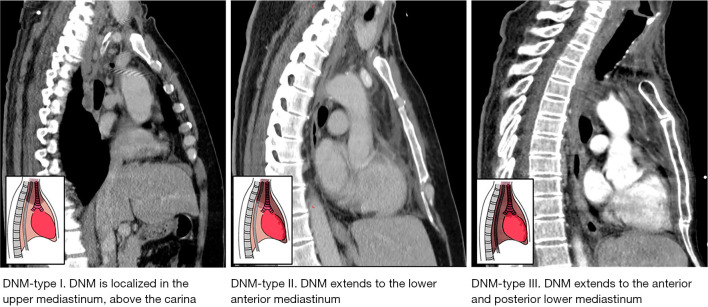

Case description: We analyze a retrospective case series of seven patients diagnosed with DNM between March 2019 and July 2022 at Hospital de la Santa Creu i Sant Pau. The primary oropharyngeal infection was peritonsillar abscess in three cases and odontogenic abscess in four. All patients showed symptoms of severe cervical infection and symptoms suggestive of mediastinitis. A cervicothoracic computed tomography (CT) scan confirmed the presence of cervical and mediastinal collections and emphysema in all cases. All patients were simultaneously evaluated by the otorhinolaryngology and thoracic surgery teams. Broad-spectrum antibiotic therapy was instituted pending culture. All the patients underwent urgent surgery, consisting of cervicotomy to control the cervical focus and unilateral or bilateral video-assisted thoracoscopic debridement and drain of the pleural cavities and mediastinum. Regarding the outcomes, no patients died, one patient (14.2%) underwent transcervical mediastino-thoracoscopy drainage only. In six patients (85.8%) we performed a combined transcervical and transthoracic approach. Reoperation was required in 3 (43%) cases. The parameter that indicated a poor clinical evolution in these patients was an increase in C-reactive protein and the infection extension on the cervicothoracic CT scan. The follow-up was 30 days from last surgery; there were no losses.

Abstract Image